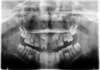

Canines incluses , traitement orthodontique 731

L'acte chirurgical de dégagement des canines incluses a été réalisé par le Dr BERTAUD

Avant